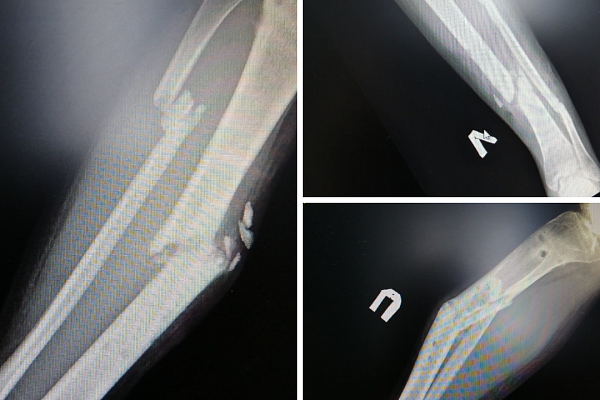

20-летний пациент оказался в травмбольнице после 8-ми месяцев безуспешного лечения за пределами Сургута. Травмы голеней молодой человек получил в ДТП. Несмотря на использование внешнего фиксатора – аппарата Илизарова – костные отломки так и не срослись. Более того, появилась деформация, образовались ложные суставы. На момент госпитализации ходить пациент не мог и передвигался в инвалидном кресле. Наши специалисты провели полный комплекс обследований и определили план лечения.

– Со второй голенью, деформация которой была более выраженной, дела обстояли сложнее. Пациенту снова наложили аппарат Илизарова, чтобы растянуть костные отломки и добиться их репозиции, – объясняет заведующий отделением ортопедо-травматологическим отделением №4 Евгений Бойко.